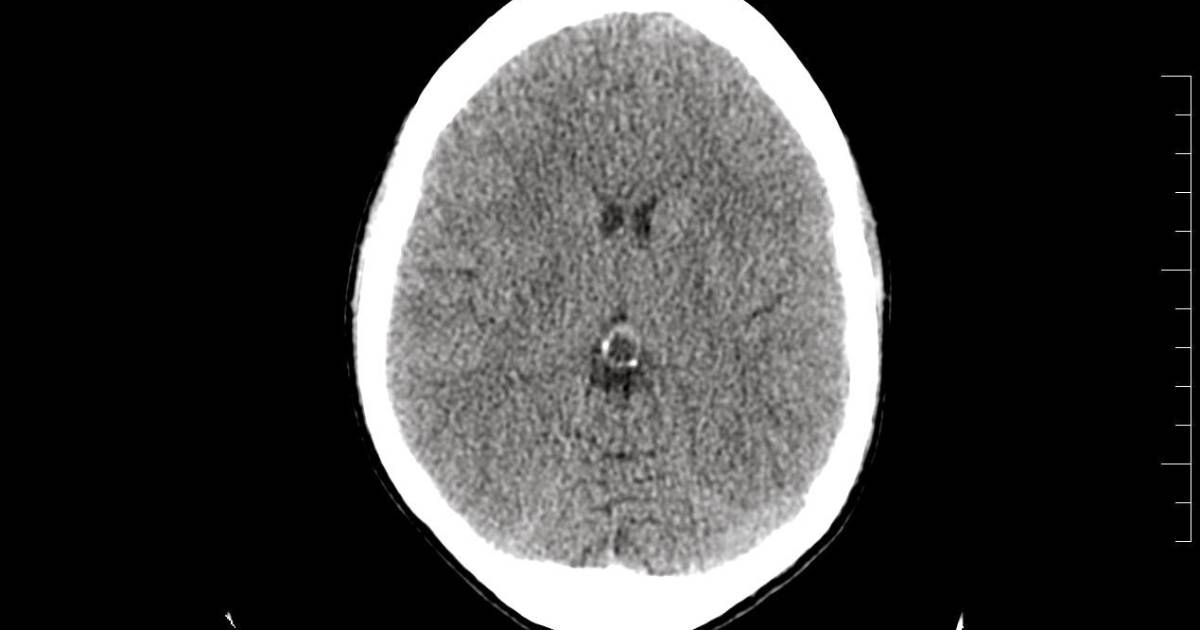

Cuando por fin le hicieron los estudios, éstos revelaron un pequeño tumor benigno en la glándula pineal, pero los doctores aseguraron que no tenía relación con su dolencia. Poco después lo regresaron al hospital debido al incremento de dolor en la cabeza acompañada de vómito. Como no podían operar el tumor lo sometieron a una punción lumbar.